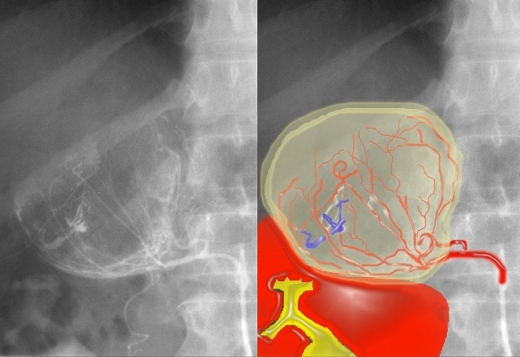

Arterial Supply – Abnormal |

| In this injection of the middle adrenal artery, a mass is apparent in the right adrenal gland. The branches of the artery are distorted and, rather than a triangular shape as seen on previous image, we see a rounded mass. There is evidence of early venous filling (blue overlay) reflecting an arteriovenous shunt, characteristic of a hypervascular tumor.Courtesy of: Ashley Davidoff, M.D. | ||